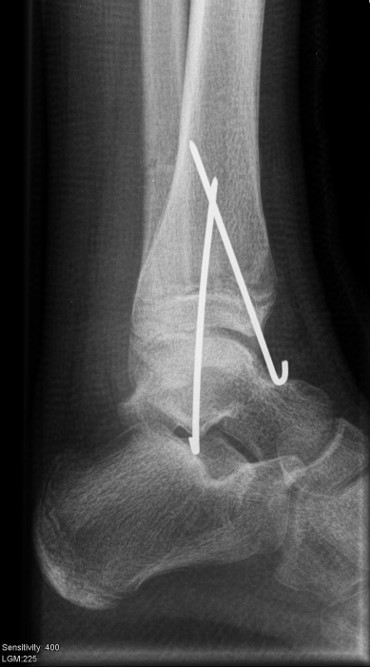

Ist die korrekte Stellung nur gegen einen federnden Widerstand zu erreichen, kann die Fraktur durch perkutane K-Drähte stabilisiert werden. Bei einer Fugenschaftfraktur mit großem Keil ist auch eine Schraubenosteosynthese möglich (Abbildungen 13 bis 14).

Behandlungsziel ist die exakte Rekonstruktion der Gelenkfläche sowie die Minimierung des Risikos einer späteren Wachstumsstörung. Dislozierte Frakturen werden offen reponiert, die Osteosynthese erfolgt mit einer Kleinfragmentschraube. Finden sich viele kleine Fragmente kann eine K-Draht Osteosynthese durchgeführt werden. Wird der Innenknöchel operiert, kann bei gleichzeitiger hochgradiger lateraler Instabilität eine Rekonstruktion des lateralen Bandapparats durchgeführt werden. Fibula Frakturen stellen sich meist spontan ein, sodass hier keine zusätzliche Osteosynthese notwendig ist.